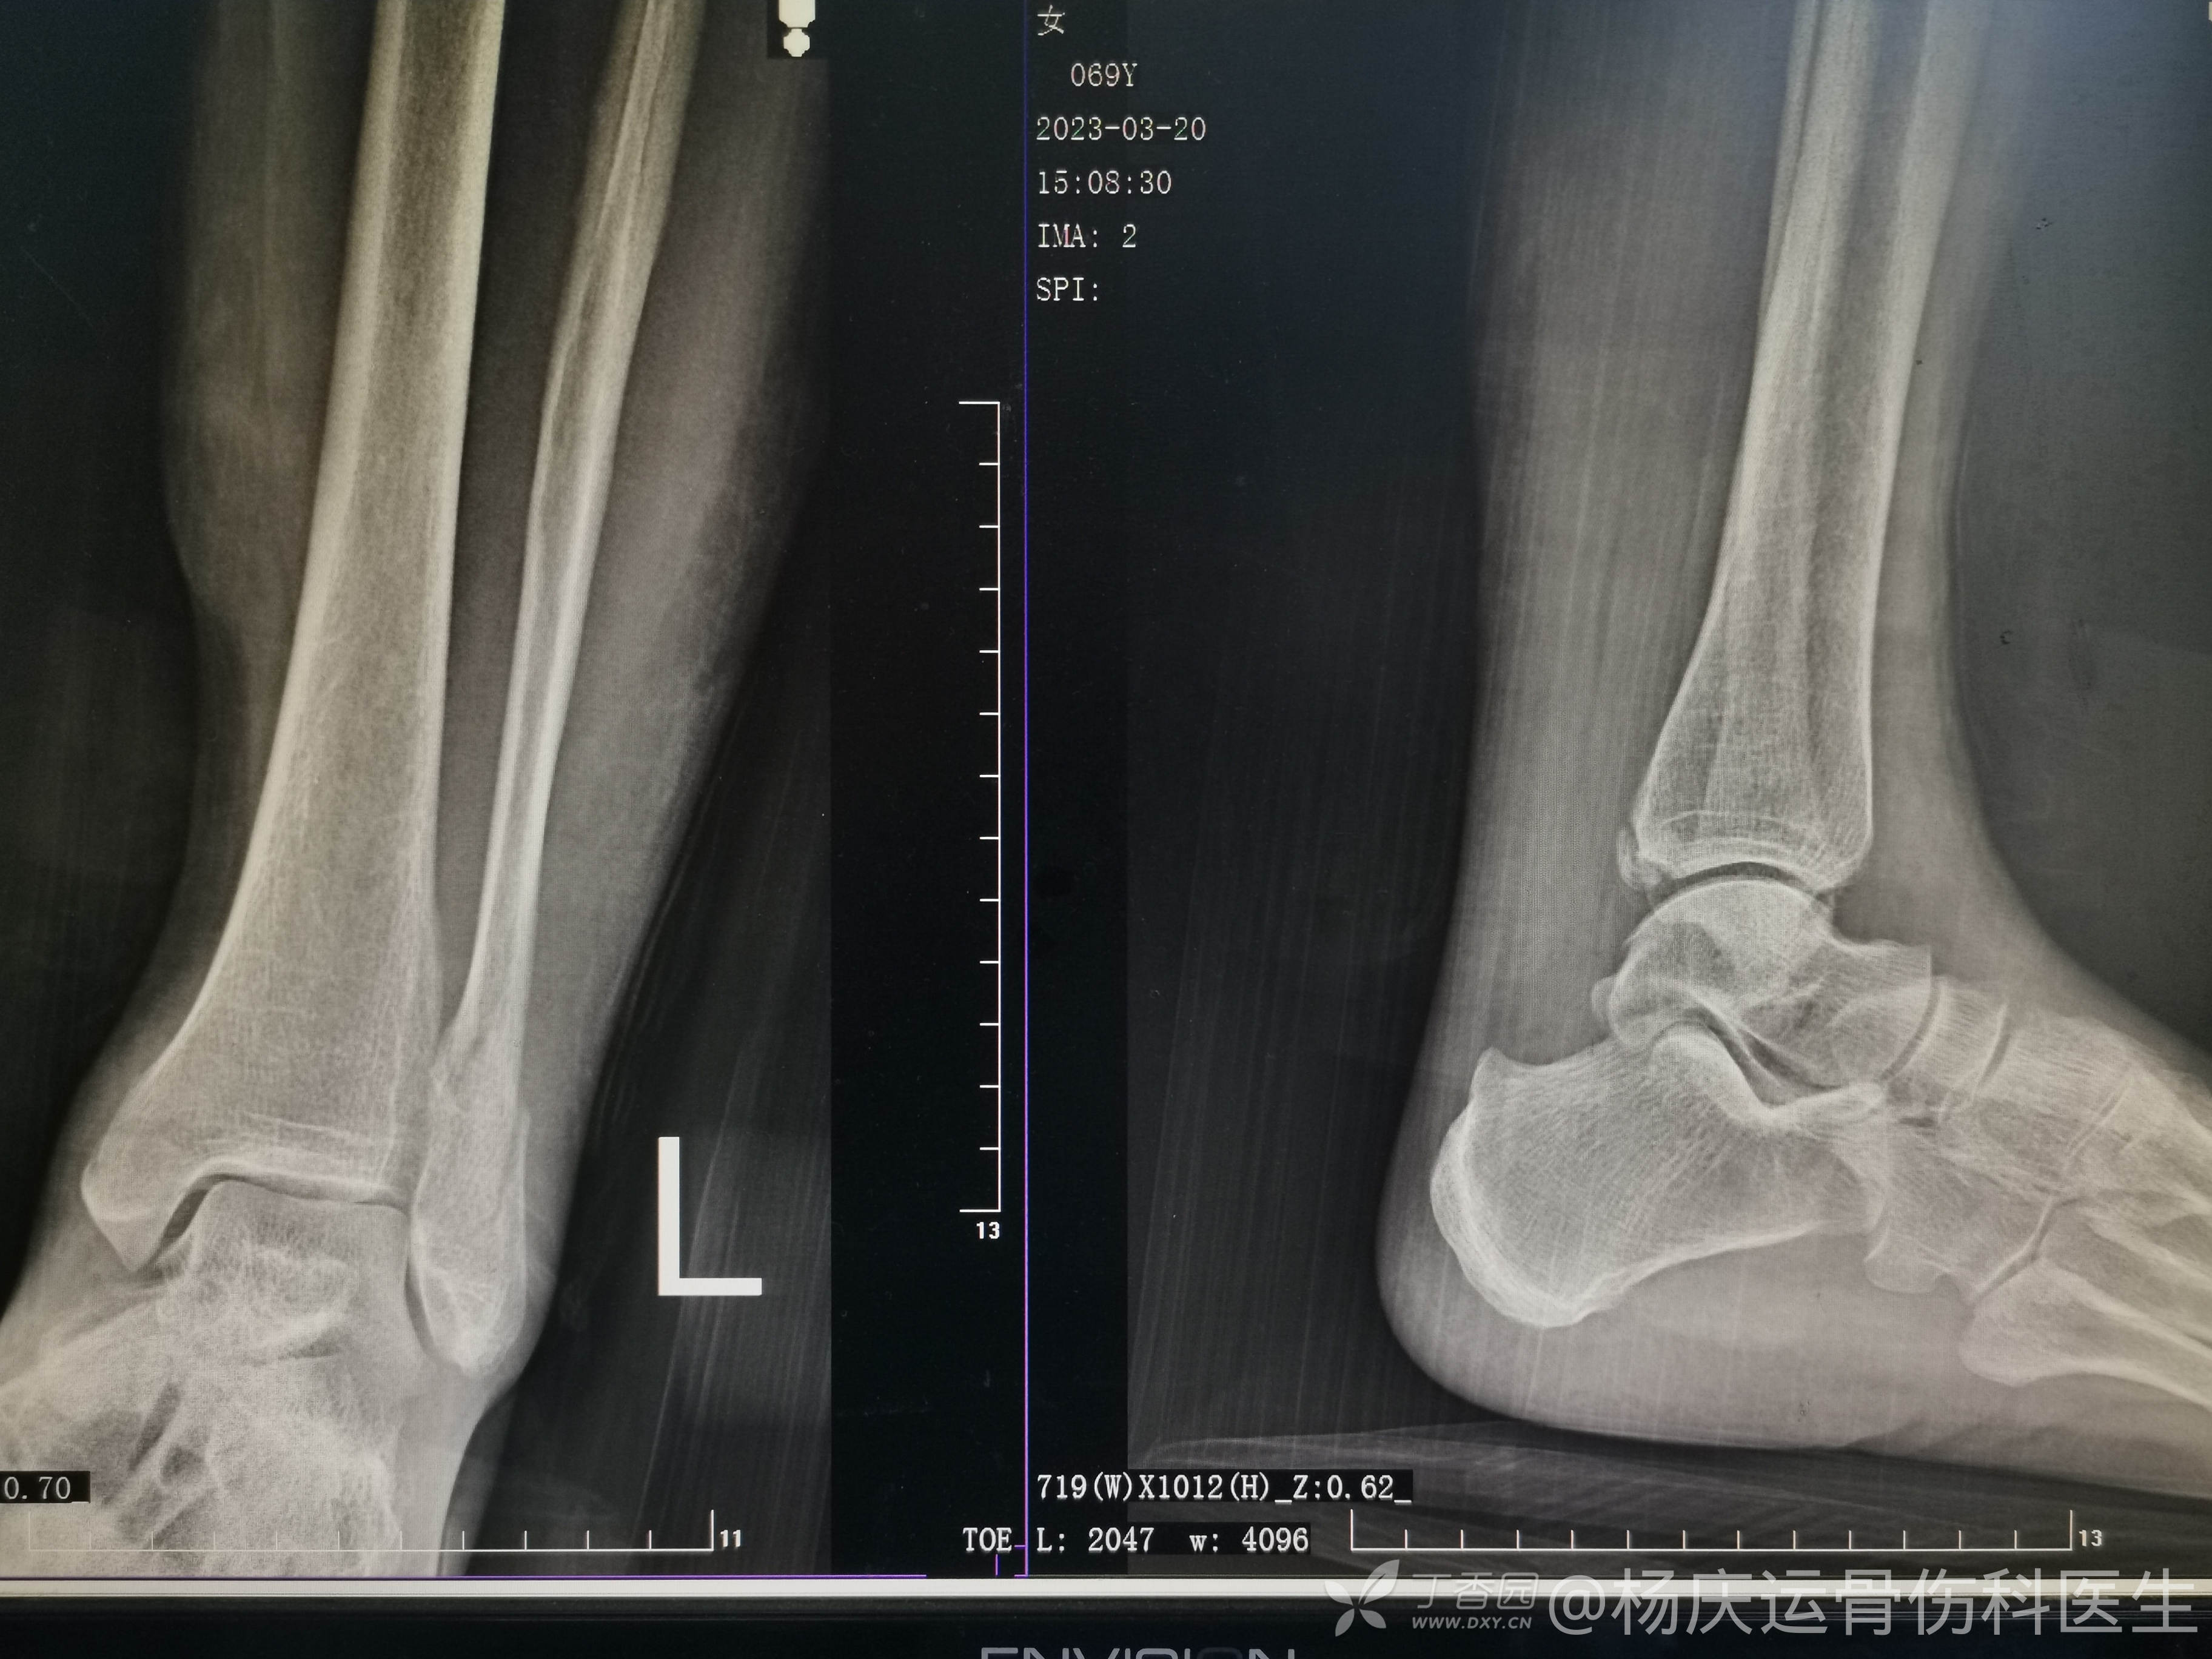

37天拍片复查,拄双拐轻负重行走